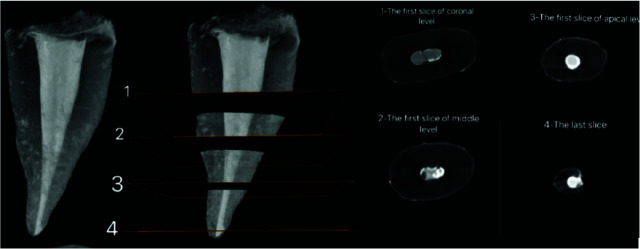

Purpose: This study was conducted to compare the quality of obturation of single-canal maxillary second premolars by the cold lateral compaction (CLC) versus continuous warm vertical condensation (CWVC) techniques using micro-CT.

Materials and method: In this experimental study, 36 extracted single-canal maxillary premolars were selected. The root canals were instrumented by Denco Blue rotary files. The teeth were randomly assigned to three groups (n=12) of control (no root filling), root canal obturation with CLC technique, and root canal obturation with CWVC technique. Next, they underwent micro-CT, and the mean volume and volume percentage (VP) of voids were calculated in the apical, middle, and coronal thirds of the root canals. Data were analyzed using one-way ANOVA, the Kruskal-Wallis, Mann-Whitney U, Bonferroni, Dunnett, Tukey, and independent t-tests (p Value<0.05).